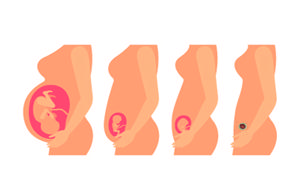

从国家放开二胎政策后,很多生了一个孩子的父母都在想一个问题,也是很多父母的疑虑,那就是到底要不要生第二胎呢?不生怕一个孩子以后会孤单,生又考虑到各种现实的问题,让人很是头疼,那么如何从长远看要不要生二胎呢?

怀孕的女性到了孕晚期都会时刻关注自己肚子里面胎儿的情况,这个时候胎动次数就会增加,胎动情况也会变得更强,孩子在肚子里面会出现各种各样的动作,很多孕妇到了怀孕晚期会感觉肚子在一抖一抖的,下面就给大家介绍一下孕晚期肚子一抖一抖的怎么回事?

孕晚期肚子一抖一抖的怎么回事

胎宝宝在准妈妈的肚子里出现一抖一抖的情况,大部分情况是正常的胎动。胎动指的是胎儿在子宫腔里的活动冲击到子宫壁的动作。一般情况下,怀孕满4个月后,即从第5个月开始母体可明显感到胎儿的活动,胎儿在子宫内伸手、踢腿、冲击子宫壁,这就是胎动。胎动的次数多少、快慢强弱等表示胎儿的安危。正常显胎动1小时不少于3~5次,12小时明显胎动次数为30~40次以上。

上面给大家介绍的就是“孕晚期肚子一抖一抖的怎么回事?”的内容,大家应该也知道这是宝宝在肚子里面做运动,只要没有出现什么异常情况一般都是正常的,每一个孩子在妈妈肚子里面的情况都有所不同,只要胎动是有规律的,证明孩子的发育非常良好,没有必要过分担心。

孕晚期胎动厉害

每一位妈妈都会经历孕晚期胎动厉害的时期,她们都知道胎动是指胎儿在子宫内的活动,一般在孕5月后孕妈妈就可以感受到胎动。胎儿会在子宫内做各种动作,注入伸手、踢腿等,这些动作会冲击到子宫壁,让妈妈有明显的感觉。胎动是胎儿在妈妈子宫里的活动,因此其次数、强弱快慢都能反映出宝宝健康安全与否。一般来说,孕晚期胎动厉害,很多孕妈妈便会担心是不是宝宝出了什么问题。其实这是再正常不过的事情了,一起来了解一下孕晚期胎动厉害。